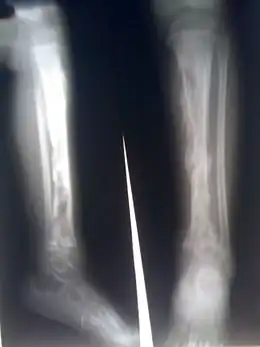

Bilan radiographique

Les radiographies standard de face, profil complété par des clichés comparatifs et de 3/4 en cas de doute sur une lésion. Au stade du début, on recherche un flou des parties molles adjacentes à la métaphyse. À la phase d'état, on recherche une apposition de fines lamelles osseuses à la corticale métaphysaire correspondant à la réaction périostée. Plus tardivement apparaissent :

- des lacunes métaphysaires ;

- des irrégularités des corticales ;

- des séquestres osseux (fragment osseux d'aspect dense libre et irrégulier).

L'aspect radiographique de certaines tumeurs malignes, tel que le sarcome d'Ewing, peut simuler une ostéomyélite. Le diagnostic doit être évoqué en cas d'évolution torpide ou atypique et confirmé par une biopsie chirurgicale.